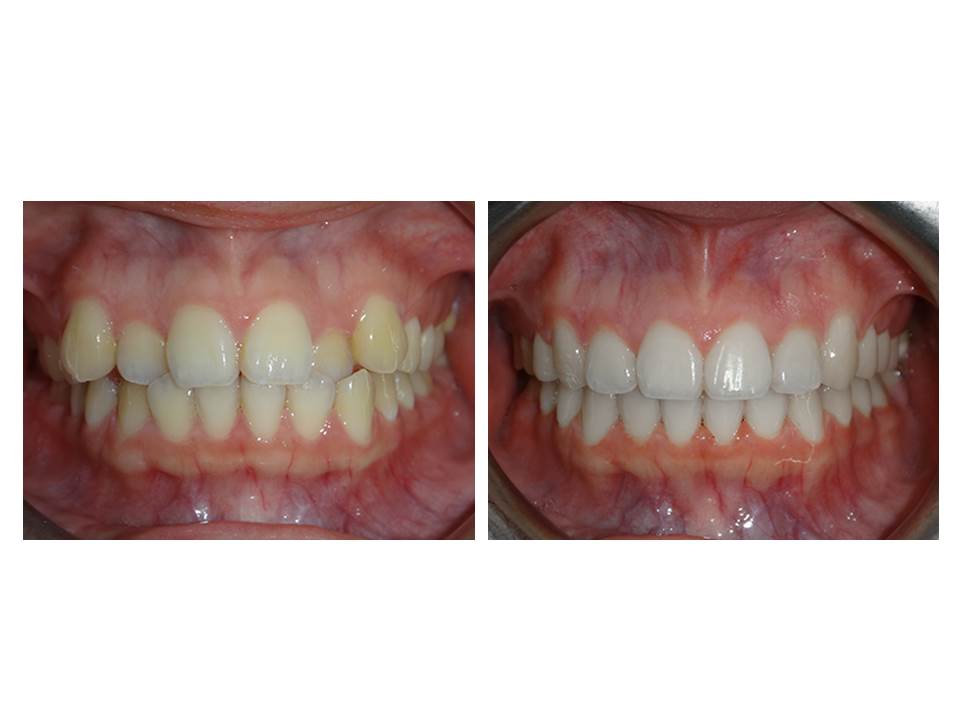

自鎖式矯正器不拔牙矯正

矯正訴求:■ 前牙錯咬 ■ 牙齒凌亂